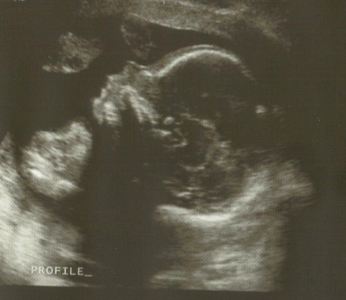

We got up this morning and headed to the clinic to view the innards of my stomach which are almost entirely being occupied by a very wiggly and flexible baby. All the organs look healthy and though it was curled up in the most uncomfortable looking position, the bones and spine are fantastic. The head shot was difficult to get as it was constantly gnawing on its hands. I figure I should eat more because of this. (I’ll take any excuse for more ice cream.)

Meet Lucy Christine, my pretty little girl. I love her so much already. I have always wanted to name a girl Lucy so that was easy. Christine is Mr. Pilver’s mother’s name. She passed about 6 years ago. Mr. Pilver and his whole family talk about her with the greatest love and respect and I wish so badly I could have known her better.